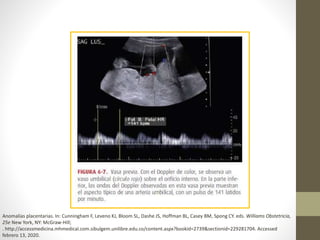

Imagenología

• El dato ecográfico, ya

sea de inserción

velamentosa del cordón

o de placenta con un

lóbulo accesorio, deben

impulsar a los

profesionales a evaluar

la posibilidad de vasa

previa